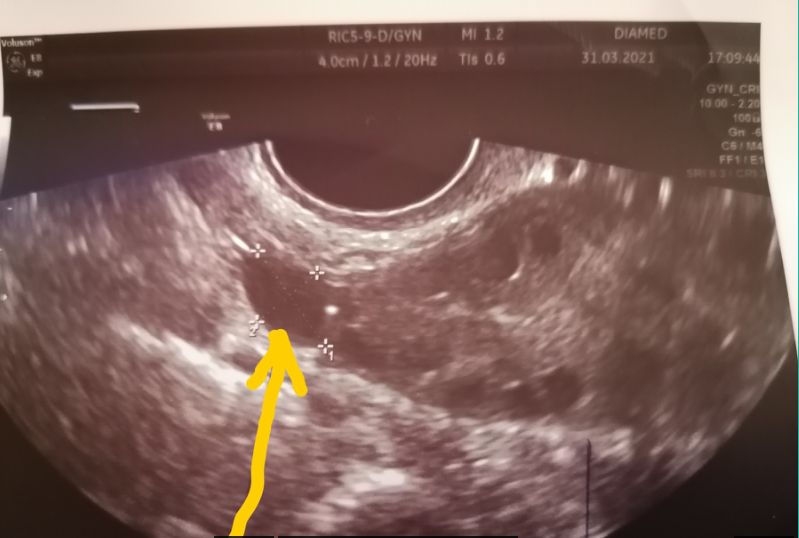

Помогите,не проходите мимо!Что это по-вашему на снимке?

Либо фолликулярная киста на самом краю яичника, либо параовариальная. Сомневаюсь, что это трубное образование. А яичник на снимке левый или правый?

yagoda_malina, мне кажется, это вообще доминантный фолликул, просто ракурс у него неудачный. Тем более что есть кровоток активный.

yagoda_malina, похоже на формирующейся жт, но у него должен быть кровоток и узист должен был его увидеть

узист включала вот эту штуку,когда цветным показывает,было много оранжевого цвета в этом месте.

yagoda_malina, с большой долей вероятности это сосуд крупный

Возможно параовариальная киста. У меня есть наподобие, только побольше вашей, висит на трубе. Уже лет 7-8 точно. Не растёт и ничему не мешает.

Это в динамике надо смотреть. Сосуд или труба расширена.